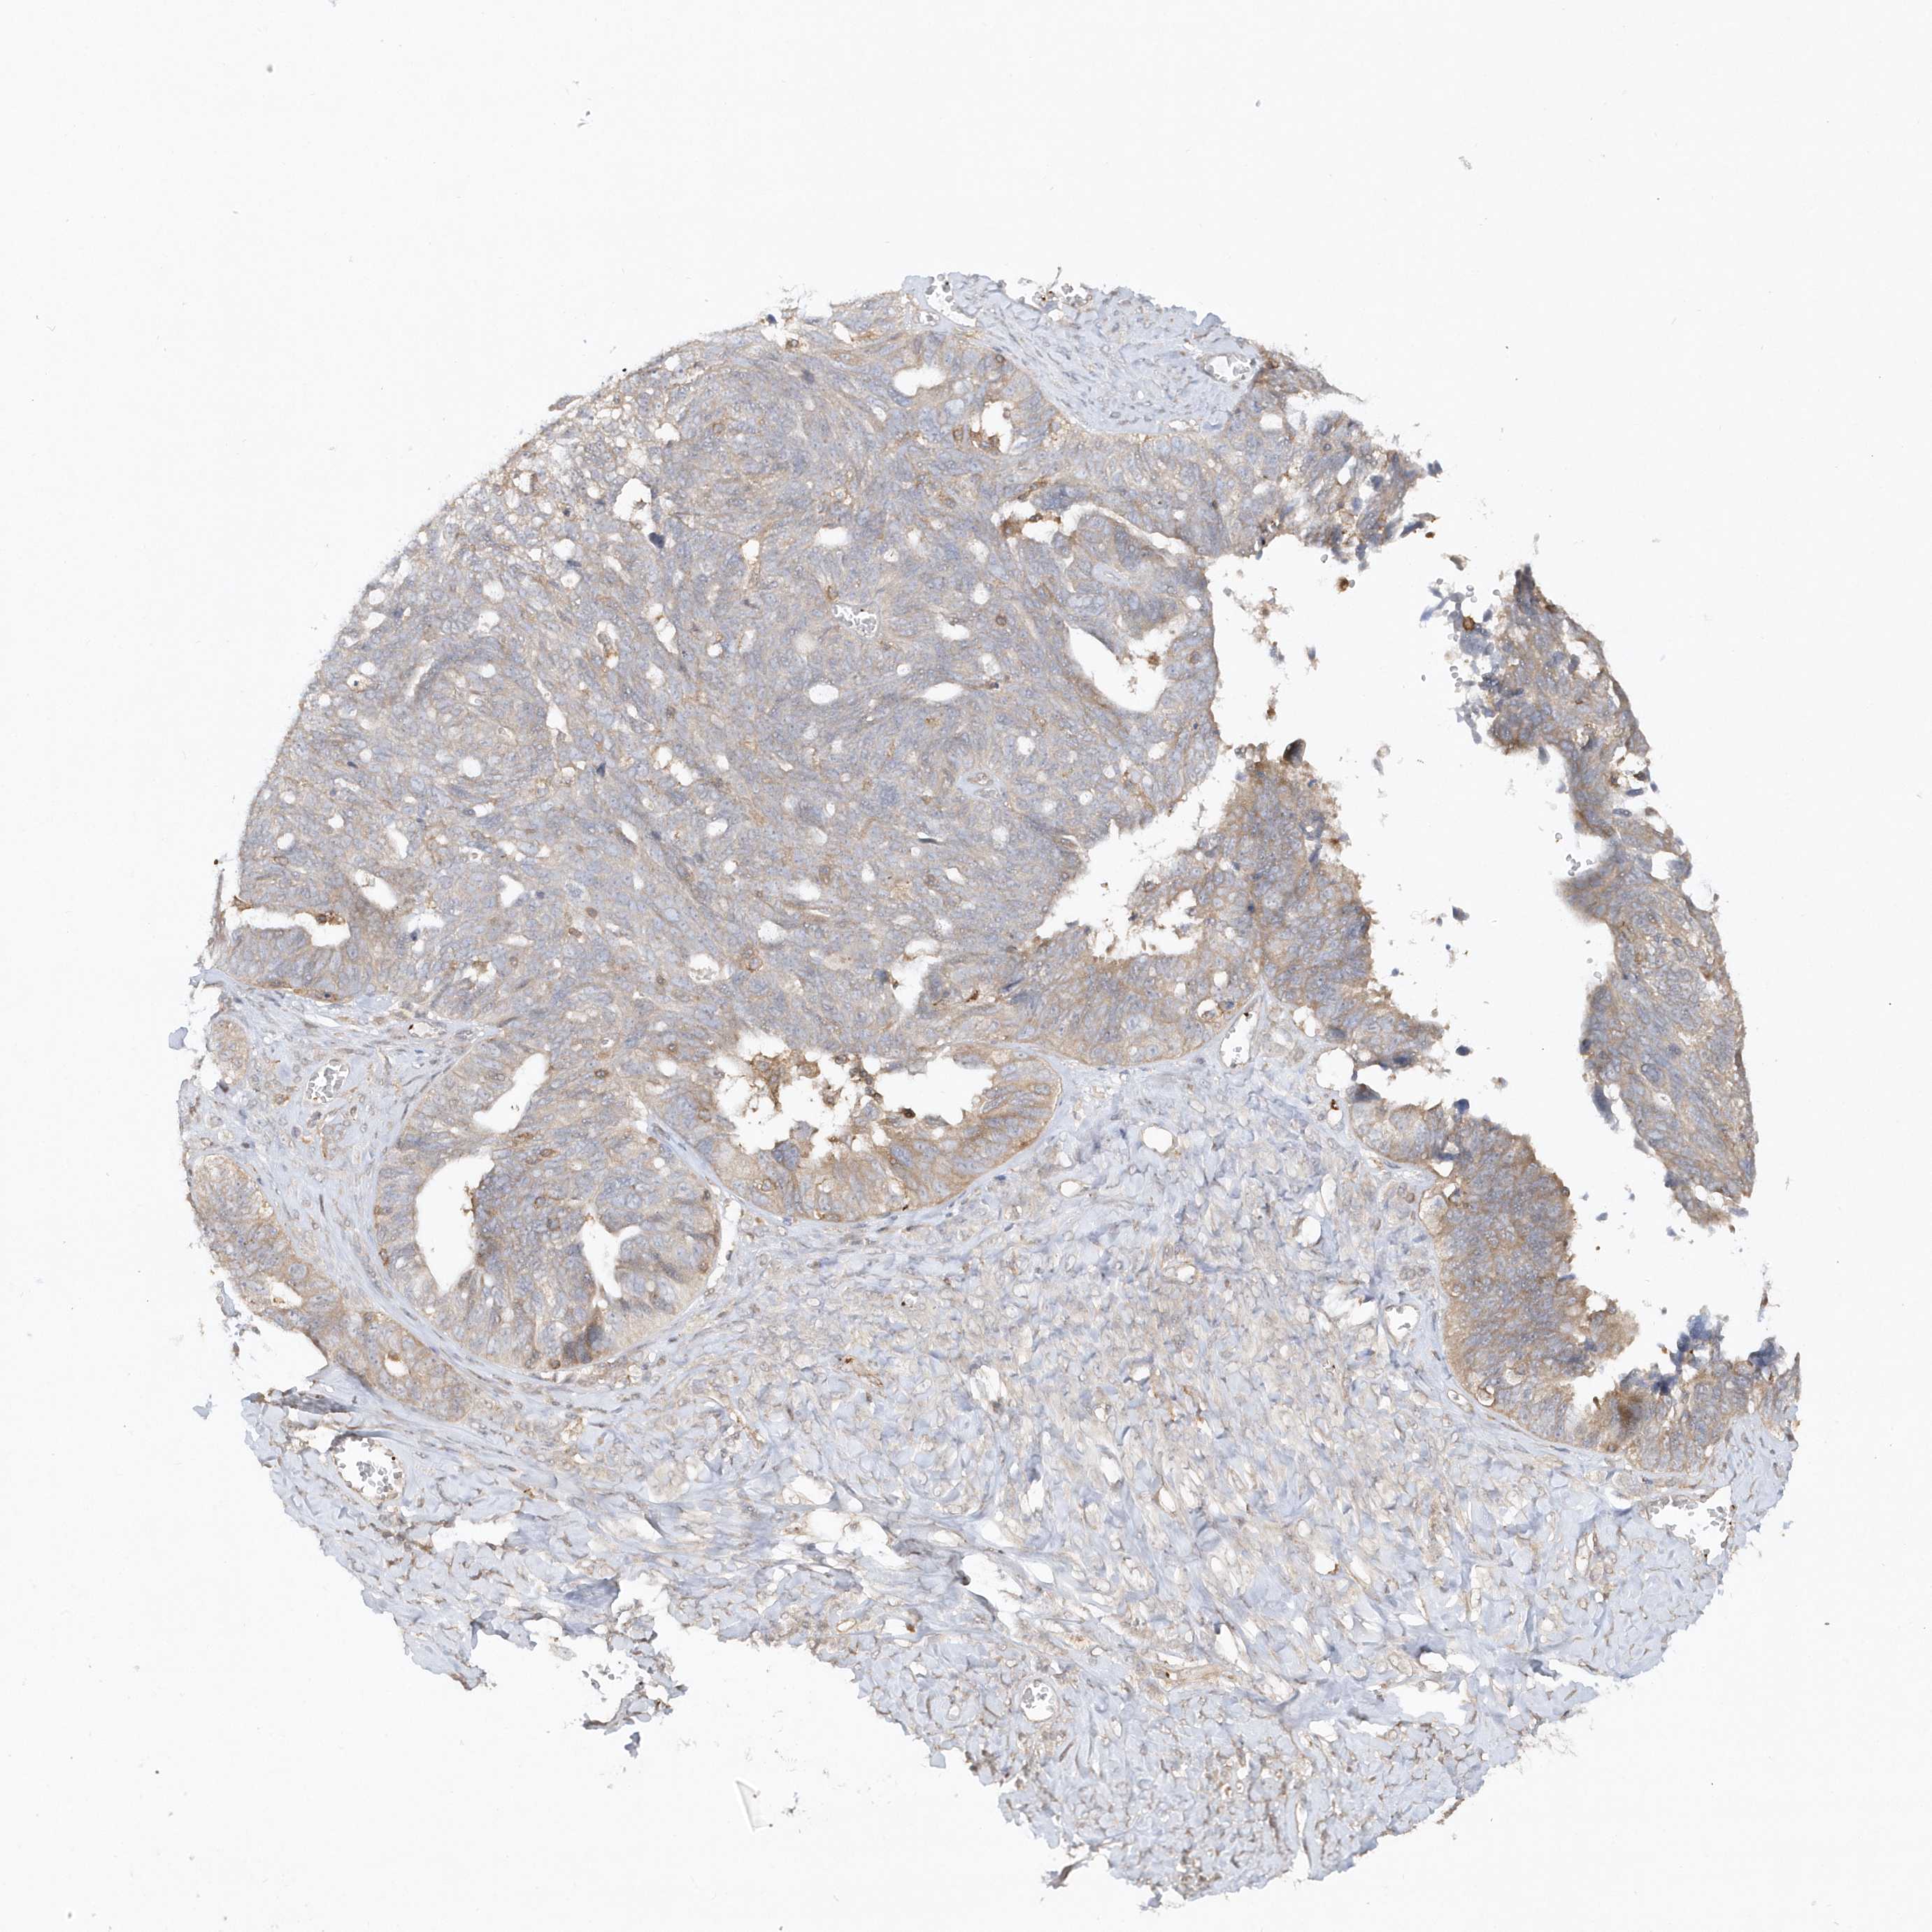

OVARIAN CANCER - Protein expressioni

A mouse-over function shows sample information and annotation data. Click on an image to view it in a full screen mode. Samples can be filtered based on level of antibody staining by selecting one or several of the following categories: high, medium, low and not detected. The assay and annotation is described here.

Note that samples used for immunohistochemistry by the Human Protein Atlas do not correspond to samples in the TCGA dataset.

Antibody stainingi

Antibody staining in the annotated cell types in the current human tissue is reported as not detected, low, medium, or high, based on conventional immunohistochemistry profiling in selected tissues. This score is based on the combination of the staining intensity and fraction of stained cells.

Each image is clickable and will lead to virtual microscopy that enables deeper exploration of all samples and also displays staining intensity scores, fraction scores and subcellular localization as well as patient and tissue information for each sample.

Antibody HPA034757

Staining

Cystadenocarcinoma, serous, NOS